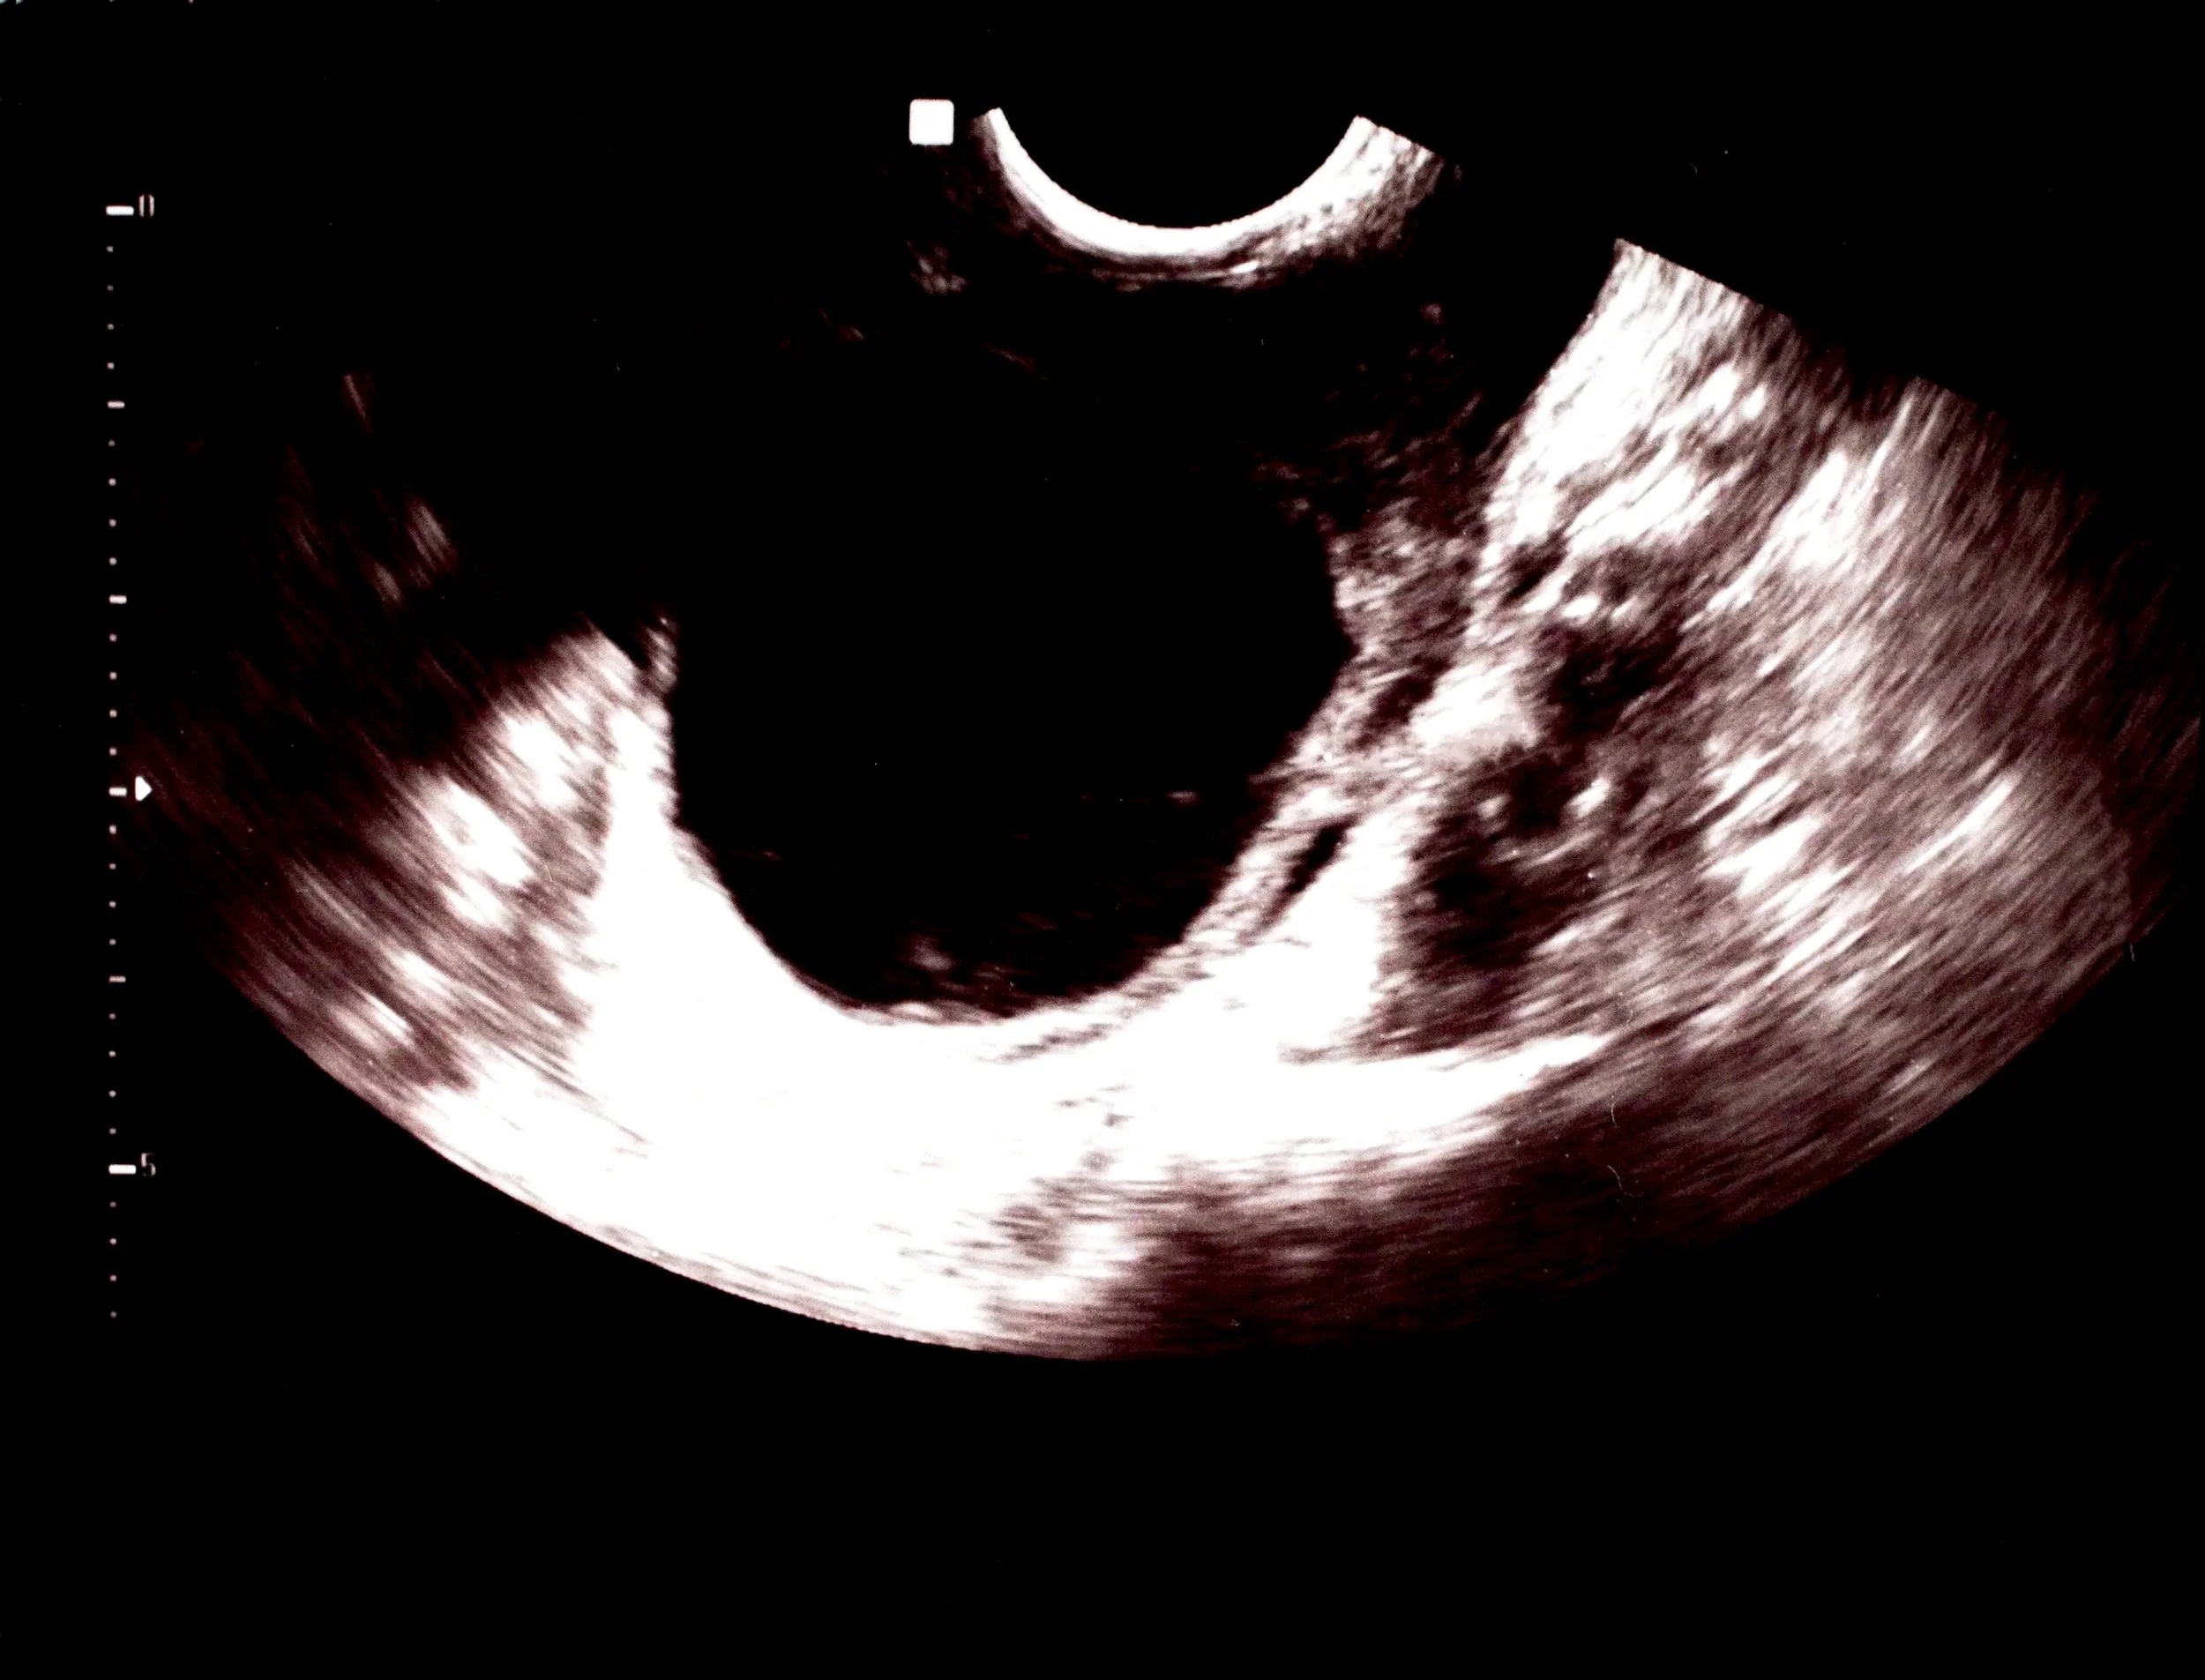

Pelvic Ultrasound Scan

• Usually the first-line investigation.

• Helps determine the size, number, and appearance of the cyst(s).

• A transvaginal ultrasound generally gives the most detailed information.

• In some cases, additional tests (such as blood tests or MRI) may be recommended depending on the ultrasound findings and your age.